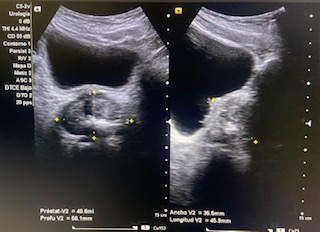

Informe ecográfico:

Riñones sin alteraciones.

Vejiga bien repleccionada sin alteraciones a simple vista.

Volumen residual: 243 ml. Próstata de contornos regulares y ecogenicidad homogénea a simple vista. Volumen prostático: 49 cc.

En ecografía determinamos el tamaño de la próstata mayor de 20 cc, por tanto se trata de una HBP grado II. La medición del RPM nos permitió detectar que el paciente presentaba residuos elevados (243 ml).